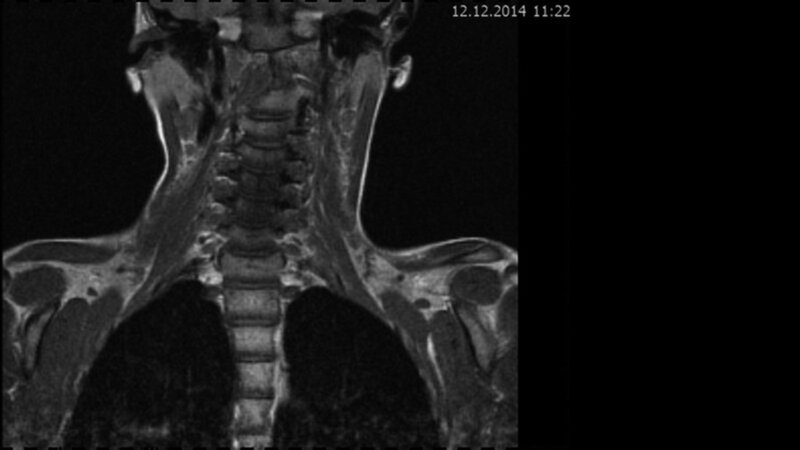

Das Fallbeispiel 1 zeigt im Verlauf eine Komplikation bei einer Arnold-Chiari-Malformation Typ 1 bei einem zum Zeitpunkt der Erstdiagnose 12-jährigen Jungen. Dieser hatte im Sportunterricht einen schweren Medizinball geköpft und ein Stauchungs-trauma der Halswirbelsäule erlitten. Nach anfänglich symptomatischer frustraner Therapie wurde er vom behandelnden Orthopäden zur MRT der HWS überwiesen. Es wurde eine Streckfehlhaltung und flachbogig rechtskonvexe Skoliose diagnostiziert, klinisch bestand ein Torticollis. Eine knöcherne oder ligamentäre Verletzung wie auch eine Schädigung des Rückenmarks bzw. eine intraspinale Bandscheibendislokation konnten bildmorphologisch ausgeschlossen werden.

Trotz weiterer Schmerz- und Physiotherapie konnte keine Beschwerdereduktion erreicht werden. 2 Monate später erfolgte eine MRT des Kopfes zum Ausschluss einer posttraumatischen Veränderung.

Bei dieser Untersuchung wurde übersehen, dass die Kleinhirntonsillen in das Foramen magnum disloziert waren und eine Arnold-Chiari-Malformation mit Erweiterung des 4. Ventrikels und des Aquäduktes inklusive Kleinhirntonsillentiefstand vorlag. Bei zwischenzeitlich auswärtig erfolgtem CT der HWS wurde eine Anlagestörung im kraniozervikalen Übergang beschrieben. Eine Kontrolluntersuchung des Kopfes weitere 4 Monate später dokumentierte neben einem medullären Ödem einen progredienten Tonsillentiefstand, der zur neurochirurgischen Behandlung mit operativer Erweiterung des Foramen magnum führte.